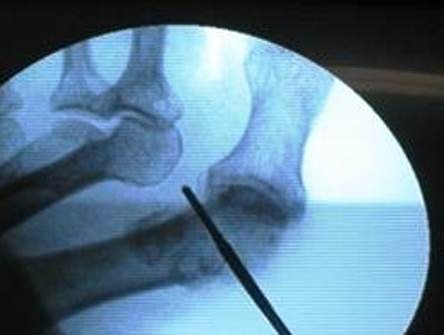

Osteotomía distal del primer metatarsiano: por la misma incisión empleada para realizar la exostectomía, se practica, con fresa Shannon 44, la osteotomía descrita por Isham –modificación de la osteotomía de Reverden– de trazo oblicuo dorsal-distal y plantar-proximal, de 45° aproximadamente, y con cuña interna (Figura No.3).

Figura No.3. Osteotomía distal del primer metatarsiano a visión radiológica.